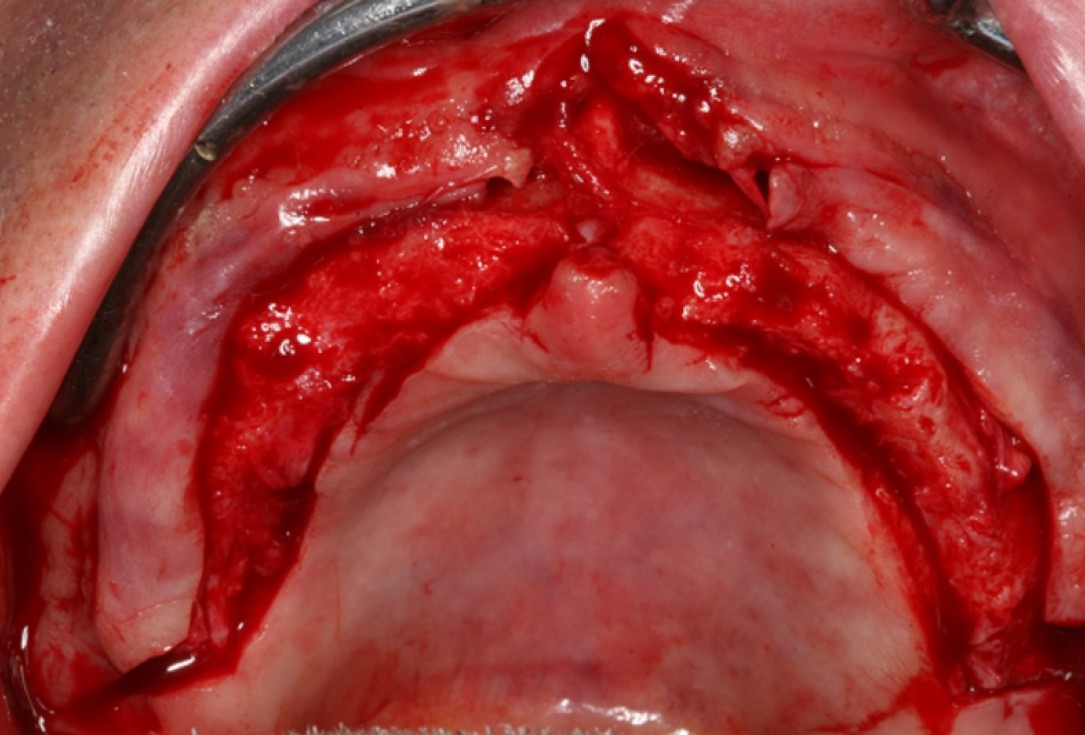

01/10 - Surgical presentation of the alveolar ridge with reduced amount of horizontal bone availableCircular bone splitting with maxresorb® & collprotect® membrane - PD Dr. J. Neugebauer